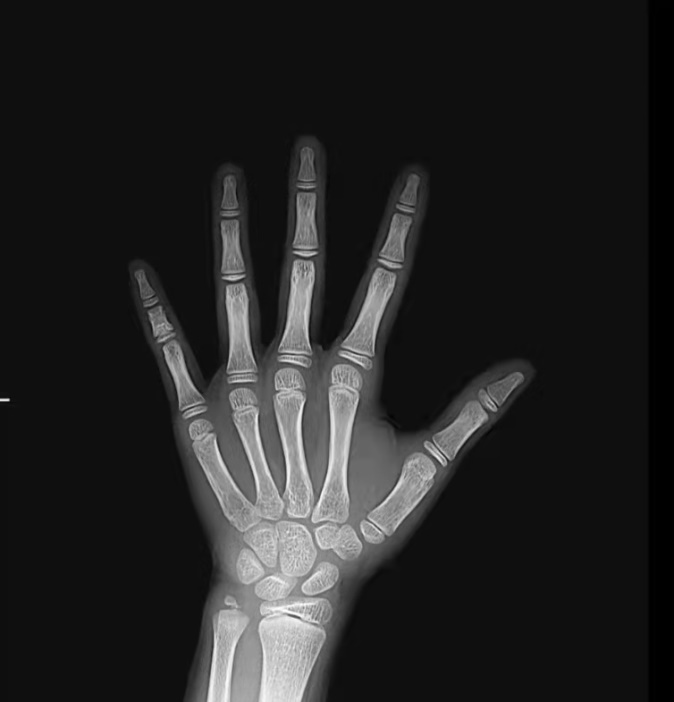

相比于年龄,骨龄更能准确地反映孩子骨骼的成熟度,是评估儿童体格发育情况的核心指标。人的生长发育可用两个“年龄”来表示,即生活年龄(日历年龄)和生物学年龄(骨龄)。骨龄是指骨骼生长的年龄,可借助于X线检查长骨干骺端的骨化中心进行判断,了解骨化中心出现的时间、数目、形态的变化及干骺愈合程度等,并与骨发育标准进行比较获得个体骨成熟的年龄。通常拍摄人左手手腕部的X光片观察掌指骨、腕骨及桡尺骨下端的骨化中心的发育程度。骨龄是评估剩余生长潜力的有效依据,比实际年龄更能反映个体发育水平和骨骼的成熟度。也就是说孩子能长多高,不取决于年龄,取决于骨龄。一般来说,女孩骨龄达到14岁,男孩骨龄达到16岁,骨龄就已经接近闭合,骨骺线未闭合,才意味着孩子还可以长高。